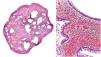

Estudio histológico de la lesión (hematoxilina & eosina, microfotografías). Izquierda (2×): corte transversal del pólipo. Se observa dilatación glandular acompañada de espacios quísticos en la lámina propia. Derecha (10×): revestimiento glandular por epitelio de células cubicas acompañadas de células caliciformes. Congestión vascular, infiltrado linfoplasmocitario y marcada eosinofilia.